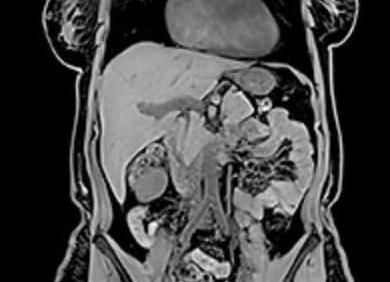

МРТ (магнитно-резонансная томография) является одной из самых информативных и популярных методик диагностирования. МРТ применяется в исследовании практически всех систем организма, в том числе и органов кишечного тракта. Воздействие МР-томографа представляет абсолютную безвредность и безопасность для здоровья человека, так как технология аппаратуры основана на сильном магнитном поле, и в ходе процедуры не применяются лучи рентгена. МРТ имеет множество преимуществ перед другими диагностическими технологиями, но в качестве самостоятельного метода не всегда дает возможность детальной визуализации полной клинической картины. Зачастую МР-томографию проводят в комплексе с другими методиками, которые в совокупности дополняют друг друга. Необходимо разобраться, что лучше МРТ кишечника или колоноскопия?!

Если проводить сравнение между МРТ кишечника и колоноскопией, в плане комфортности процедур лидирует магнитно-резонансная томография, так как ее проведение не доставляет боли и неприятных ощущений для пациента. Однако МР-томограф не всегда получает целостную и детальную картину органа, что обосновано специфическим строением желудочно-кишечного тракта. К примеру, желудок и пищевод качественно визуализируются на экране МРТ, но петли кишечника, наслоенные друг на друга, скрывают от сканера некоторые участки.  В таком случае, более эффективным методом является колоноскопия, так как введение эндоскопа в полость прямой кишки дает возможность просмотреть каждый сантиметр толстого кишечника, и в ходе диагностики осуществить лечебные процедуры.  В то же время тонкий кишечник и терминальные отделы толстого кишечника четко визуализируются на МРТ с контрастированием. Медицинская практика показывает, что оба метода имеют как недостатки, так и преимущества, поэтому часто проводятся в комплексе. Перед назначением диагностики, специалист изучает данные о предварительном диагнозе больного и его индивидуальных особенностях, после чего решит, что будет эффективнее колоноскопия или МРТ кишечного тракта.

МРТ кишечника или метод ирригоскопии?

Ирригоскопия – это рентгенологический метод исследования кишечного тракта, при котором в полость прямой кишки пациента вводят бариевую взвесь. Способ является атравматичным и безболезненным, но не абсолютно безопасным, так как технология процедуры предполагает небольшую дозу облучения. В связи с этим, количество обследований ирригоскопии для пациента ограничено.

Согласно общему мнению специалистов, ирригоскопия – не самый информативный метод диагностирования. Рентгенологическое исследование проводится с целью подтверждения результатов стандартной колоноскопии и визуализации невидимых для инвазивного способа областей. Однако более результативной и, к тому же, абсолютно безопасной, является методика магнитно-резонансной томографии. Поэтому, если возникает вопрос, что лучше МРТ кишечника или ирригоскопия, – ответ очевиден.

МРТ или КТ кишечника?

КТ – современная методика исследования, принцип которой основан на воздействии рентгенологических лучей. Способ имеет альтернативное название – виртуальная колоноскопия. Но в отличие от традиционной инвазивной диагностики, процедура КТ не предусматривает инвазивной эндоскопии, поэтому сканирование проводится безболезненно.

Если провести сравнение, чем лучше обследовать кишечник КТ или МРТ, то можно отметить, что обе методики дают схожие результаты. Компьютерная, как и МР-томография, могут быть не достаточно информативными в выявлении образования, размером менее 0, 1 см. Благодаря МРТ можно детально изучить состояние и структуру мягких тканей, а также характер патологии в них, степень поражения, и распространенность аномального процесса. Как и МРТ с контрастом, КТ с высокой точностью визуализирует кровоизлияния, гематомы и новообразования. По уровню безопасности безупречным лидером является МРТ, так как МР-томограф создает магнитное поле, не приносящее вреда здоровью, и допускается к проведению даже при беременности. Однако существуют противопоказания к МРТ (металлические предметы в теле пациента, протезирования, осколки, боязнь замкнутого пространства и т. д.) В таких случаях назначается компьютерная томография.

Ирригоскопия – рентгеновский метод исследования толстой кишки, предусматривающий ее тугое заполнение бариевой взвесью, с последующим опорожнением и раздуванием кишки воздухом.

Альтернативой вышеуказанному методу является гидро-магнитно-резонансная томография, позволяющая визуализировать тонкую и толстую кишки. Метод основан на двойном контрастировании стенки кишки за счет скопления жидкости в ее полости и внутривенного введения препарата, позволяющего контрастировать стенки кишки.

Однако оба метода уступают колоноскопии – визуальному осмотру и оценке состояния внутренней поверхности (слизистой оболочки) толстой кишки при помощи специального зонда – эндоскопа.